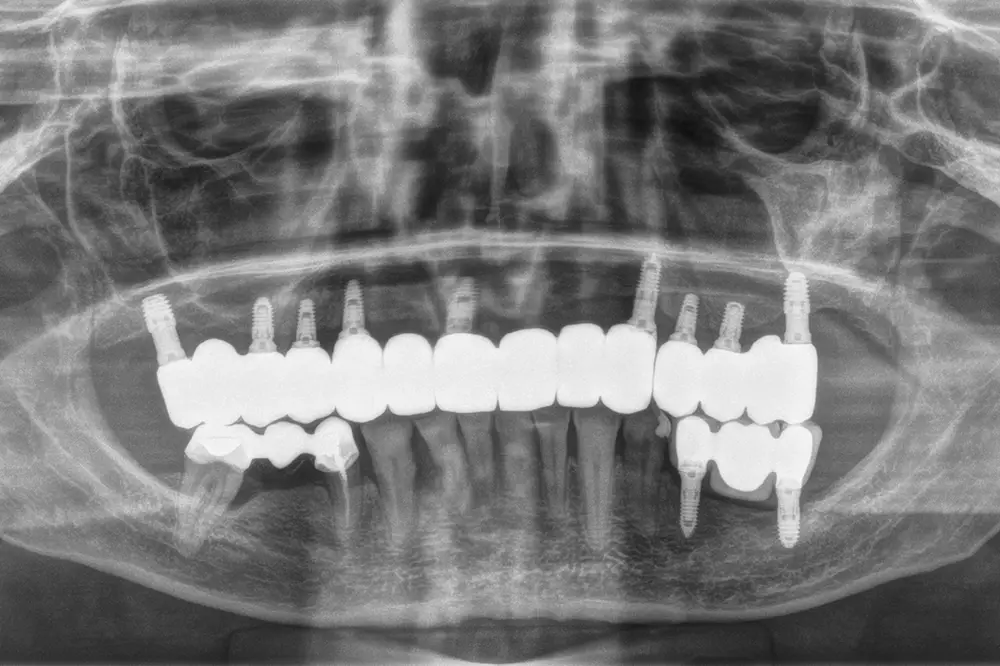

Para los sectores posteriores, se fabricaron estructuras mediante fresado CAD/CAM del mismo modo que la barra anteriormente descrita, con la diferencia de que sobre ellas se colocó un recubrimiento de cerámica (figs. 47-49). La paciente continúa en seguimiento, sin evidenciarse pérdidas óseas significativas en ninguno de los implantes estrechos y cortos que conforman la restauración de todo el maxilar superior tras tres años de carga de la prótesis definitiva (y hasta 4,5 de la carga de los implantes de la fase inicial de carga inmediata) (fig. 50).

Fig. 49. Radiografía final en el momento de colocación de la prótesis, dividida en los tres sectores.

Fig. 50. Imagen radiográfica de la paciente a los 3 años de la carga definitiva y 4,5 años tras la carga inicial de los implantes colocados inicialmente para la carga inmediata. En ella vemos la estabilidad del tratamiento en el tiempo de seguimiento ofrecido.